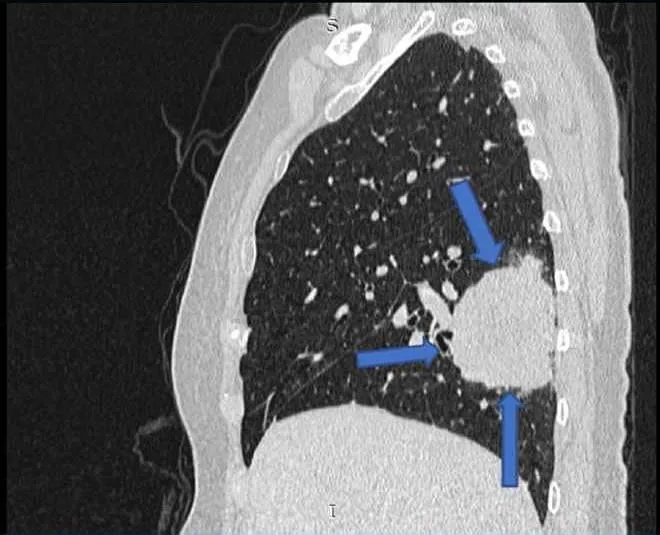

她第一次就诊时的常规胸片(图1)检查偶然发现了右肺肿块。随后的胸部增强计算机断层扫描(CT)(图2)显示肺右下叶后基底段的肺肿块大小为4.7×7.0×7.0 cm(前后×宽度×头尾)。肿块附近也有卫星结节。对肿瘤进行支气管镜活检,组织病理学检查(HPE)结果显示腺癌,证实为原发性肺恶性肿瘤,表皮生长因子受体(EGFR)基因的外显子19缺失。

图1. 胸部X线,右下肺叶有肿块

图2. 胸部计算机断层扫描显示右下叶肿块,周围有卫星结节(箭头)